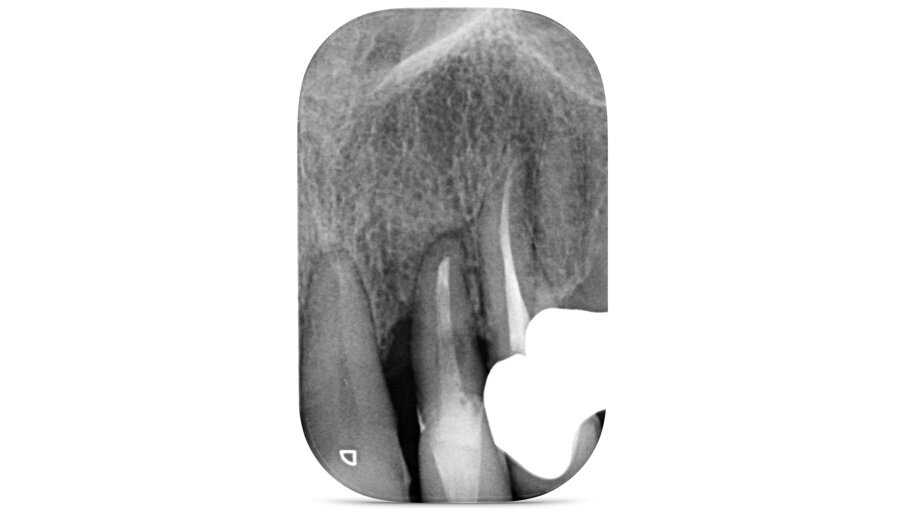

La paziente, B.G. di sesso femminile, di anni 71, è giunta alla nostra osservazione per la mobilità e lieve dolore a carico dell’elemento 2.2 (incisivo laterale superiore sinistro) (Fig. 1). All’esame ispettivo l’elemento presenta mobilità di grado 3. Al sondaggio parodontale presenta una tasca mesiale di 7 mm e di 3 mm lungo le altre superfici del dente. All’esame radiografico, eseguito con radiografia endorale periapicale, si osserva un’area di radiotrasparenza riconducibile a riassorbimento osseo soprattutto in sede mesiale (Fig. 2).

Fig. 2_Radiografia periapicale in sede 2.2.